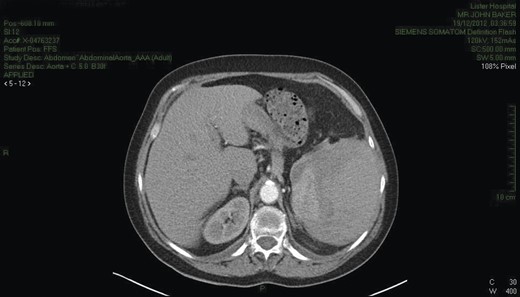

CT scan (Fig. 1) was consistent with splenic rupture. Laparotomy was performed and a large splenic haematoma with ∼1 l of blood in the abdomen and a splenectomy was performed. The postoperative period was complicated by a lower respiratory tract infection and some difficulty with mobilization but the patient made good recovery otherwise. During the post-operative period she developed a hypoglossal nerve palsy, which was assessed by the neurologist. An MRI scan failed to reveal a cause and the palsy settled spontaneously. She was discharged after 21 days.

CT chest/abdomen demonstrating a large splenic haematoma with hyper- and hypo-dense areas. High attenuation fluid is present within the pelvis consistent with blood.